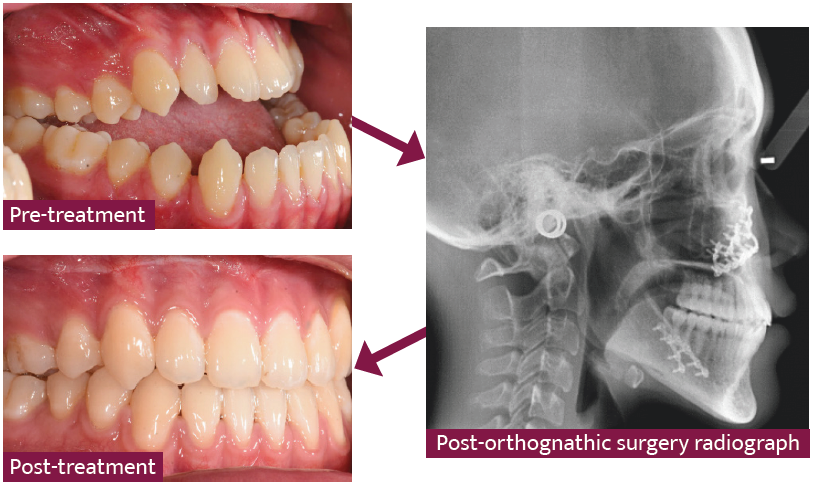

Understanding Orthognathic Surgery - Decisions In Dentistry

decisionsindentistry.comOrthodontic-orthognathic Surgical Treatment In A Patient With Class II

decisionsindentistry.comOrthodontic-orthognathic Surgical Treatment In A Patient With Class II